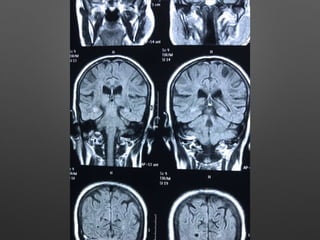

Investigations

• HB- 14.1gm% - 12.2

• WBC- 15990cells/cumm - 10770, -P 83%, L-9%,M-7%

• Platelets - 3.3lakhs - 2.8

• ESR- 63mm/hr

• RBS - 267 mg/dl

• CUE - N

• RFT - N

• LFT - N

• S.Na - 137, k+ - 3.9, Mg- 2.1, Ca- 9.1, Ph- 3.5, Ammonia- 0.29

• ECG - N

• 2DEcho- N

• U/S - Abd- Gr I Fatty liver changes

Investigations • HB- 14.1gm%- 12.2 • WBC- 15990cells/cumm - 10770, -P 83%, L-9%,M-7% • Platelets - 3.3lakhs - 2.8 • ESR- 63mm/hr • RBS - 267 mg/dl • CUE - N • RFT - N • LFT - N • S.Na - 137, k+ - 3.9, Mg- 2.1, Ca- 9.1, Ph- 3.5, Ammonia- 0.29

• 9.

• ECG -N • 2DEcho- N • U/S - Abd- Gr I Fatty liver changes